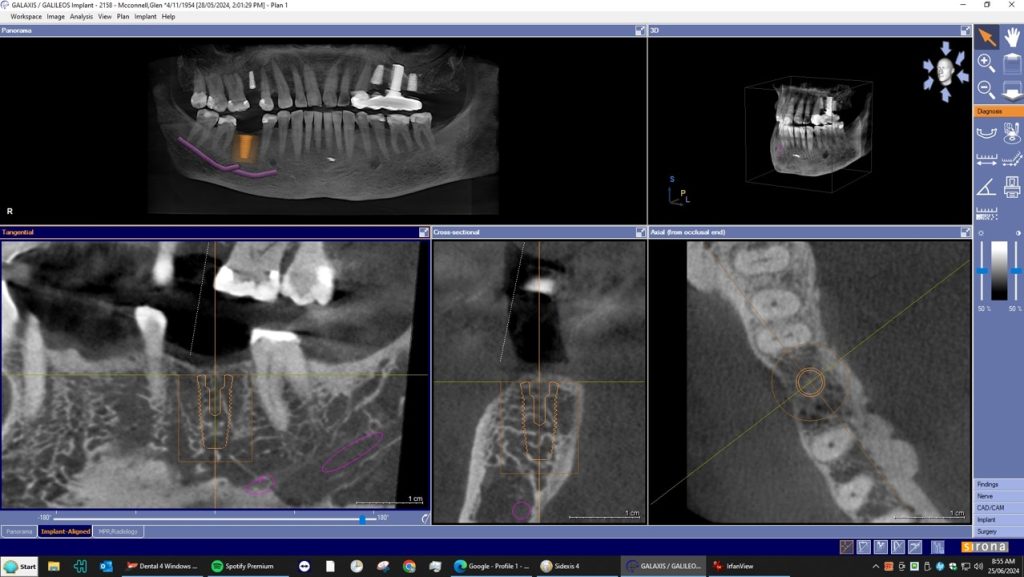

A dental Implant is a titanium “root” that integrates directly with the surrounding bone and replaces the function of the natural tooth. Neoss Implants are made using the best quality medical grade titanium, which is well known for its proven biocompatibility, and have a treated surface to facilitate bone integration.